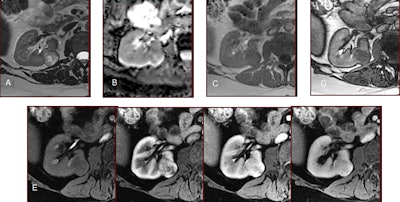

Aspect typique d'un angiomyolipome pauvre en graisse: isointense ou très discrètement hyperintense en T1 (A), sans ou avec chute de signal en opposition de phase (B), hypointense en T2 (C), avec une franche restriction de diffusion sur la cartographie ADC (D), hyperartérialisée et avec un lavage rapide (F). Image reproduite avec l'aimable autorisation du Dr Nicolas Grenier et de la Société française de radiologie (SFR) - reproduite avec l'autorisation de SFR à partir l'e-Quotidien des JFR.Le nouveau protocole IRM-mp utilisé à Bordeaux pour la différenciation tumorale est en cours de validation pour la précision du diagnostic. Les séquences utiles à cette caractérisation de tumeurs sont les suivantes:

- La séquence pondérée en T2 : elle doit absolument être réalisée en turbo ou fast spin-écho et jamais en T2 rapide en écho de gradient. Elle permet d'évaluer l'intensité de signal de la tumeur par rapport au rein : seuls les fpAML et les CP ont un signal très inférieur à celui du rein.

- La séquence pondérée en T1 en écho de gradient avec étude du déplacement chimique (Dixon) : une chute de signal peut s'observer en opposition de phase en cas de fpAML, de carcinome à cellules claires (CCC) ou de CP, et en phase en cas de CP.

- La séquence de diffusion : seuls les fpAML et les CP ont un signal très inférieur à celui du rein.

- La séquence dynamique après injection de produit de contraste permettant de « tracer » une dynamique de rehaussement : seuls les CP présentent un rehaussement très faible et très progressif.